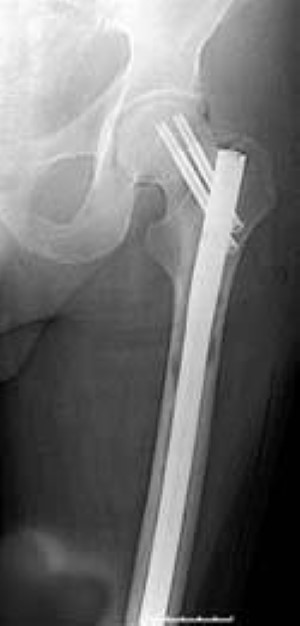

intramedullary rod in femur for MBD

An intramedullary rod has been placed down the center of the femur. The goals of bone stabilization in the lower extremity include preventing a pathologic fracture, relieving pain, and improving mobility and quality of life.